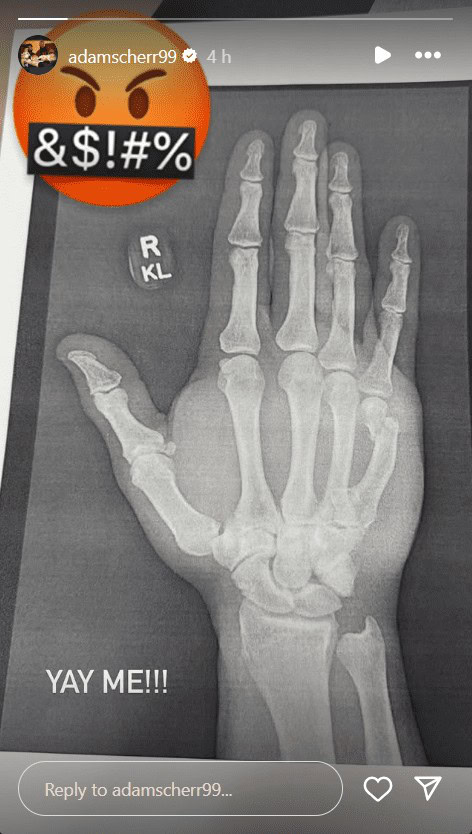

Strowman, who has stayed in peak physical shape since his WWE release in May, took to Instagram to share an X-ray of the injury. The image clearly showed the break, accompanied by an angry emoji with a censor bar across its mouth and the sarcastic caption, “YAY ME!!”